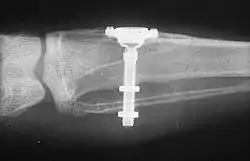

The design of implants has to account for a lifetime of real-world use in a person's mouth. Regulators and the dental implant industry have created a series of tests to determine the long-term mechanical reliability of implants in a person's mouth where the implant is struck repeatedly with increasing forces (similar in magnitude to biting) until it fails.[30]